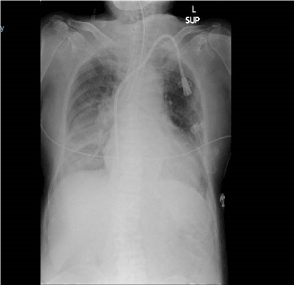

Within 5 minutes of completion of block, the patient experienced sudden onset of shortness of breath hoarseness of voice and anxiety. On examination, she had poor respiratory efforts, bilateral rhonchi with poor air entry and her SpO2 fell to 80% on room air. She was propped up and administered Salbutamol, Ipratropium nebulization followed by IV ketamine 10 mg which gave a transient improvement of her symptoms. However, she still had significantly impaired respiratory efforts with hypoxia and hypercarbia. Trachea was intubated with rapid sequence induction and positive pressure ventilation was initiated. Post intubation chest X-ray showed an underlying right lower zone consolidation with effusion without any pneumothorax or elevation of the right hemi-diaphragm. Surgery was abandoned due the unexpected complication and the patient was moved to post-anesthetic care unit (PACU). After the reversal of muscle blockade, she had low tidal volumes on spontaneous ventilation and was assisted with on pressure support ventilation.

Chest X ray done after intubation (Figure 1) excluded the pneumothorax, however it did not demonstrate elevated right hemi diaphragm since it was taken immediately after intubation which required muscle relaxation with Rocuronium. Bronchospam was confirmed clinically by auscultation and improvement of wheeze after bronchodilators. Recurrent laryngeal nerve involvement was possible due to hoarse voice and dyspnea but we could not demonstrate any vocal cord asymmetry during intubation due to the effect of muscle relaxant.

Figure 1. Chest X ray done after intubation